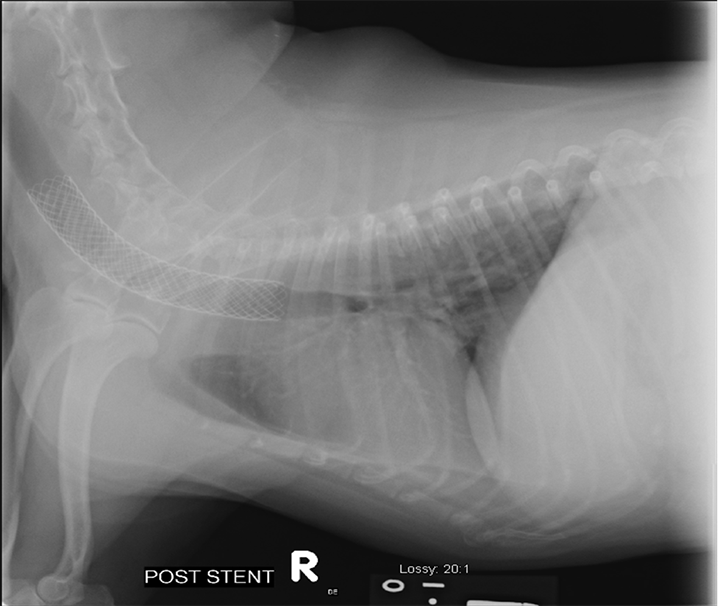

Collapsing trachea medication 2025, This right lateral radiograph demonstrates collapse of the. Download Scientific Diagram 2025

This right lateral radiograph demonstrates collapse of the. Download Scientific Diagram